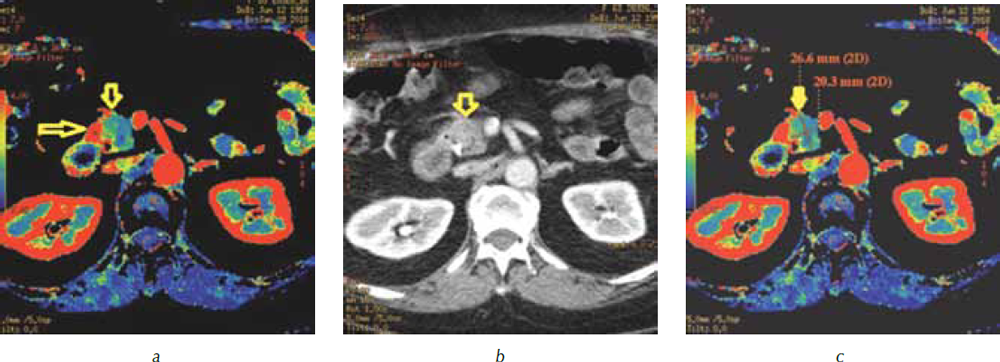

При анализе перфузионных карт был выявлен контакт опухоли на уровне конфлюэнса с правой боковой стенкой воротной вены с уплощением ее контура без признаков инвазии (рис. 6), от магистральных артерий опухоль была отделена прослойками жировой ткани.

Рис. 6. Компьютерная томография гепатопанкреатодуоденальной зоны в портальную фазу сканирования: а — трехмерная реформация в алгоритме MIP. Перешеек поджелудочной железы (стрелка) прилежит к портомезентериальному стволу, границы опухоли не видны; b — перфузионная карта скорости кровотока (BF). Опухоль (стрелка) в головке поджелудочной железы вплотную прилежит к правой боковой стенке воротной вены (стрелка) без сохранения жировой прослойки. Контур вены в месте контакта с опухолью уплощен

Полученные данные позволили расценить опухоль как резектабельную, что послужило показанием к выполнению радикального оперативного вмешательства. 01.02.2018 пациентка оперирована в объеме пилоросохраняющей панкреатодуоденальной резекции. Интраоперационно признаков инвазии опухоли в воротную вену не выявлено. При патоморфологическом исследовании установлен окончательный диагноз: «Низкодифференцированная протоковая карцинома поджелудочной железы pT2N1M0G3R0». Послеоперационный период гладкий. Пациентка выписана из стационара на 8-е сутки.

В нашем наблюдении при стандартном протоколе МСКТ нативное исследование и постконтрастное сканирование в артериальную и портальную фазы позволили выявить только косвенный признак опухоли головки поджелудочной железы в виде расширения главного панкреатического протока в области тела и хвоста, сама опухоль была не видна. Построение 3D-реформаций в артериальную фазу дало возможность установить важную при выполнении радикального вмешательства особенность строения артерий целиакомезентериального бассейна в виде отхождения правой печеночной артерии от верхней брыжеечной артерии. КТ-перфузия позволила четко визуализировать опухоль, определить ее границы, выявить распространение на область перешейка поджелудочной железы. По параметрическим картам были определены размеры опухоли, измерены показатели перфузии, соответствовавшие аденокарциноме, доказано отсутствие инвазии магистральных висцеральных артерий и вен.